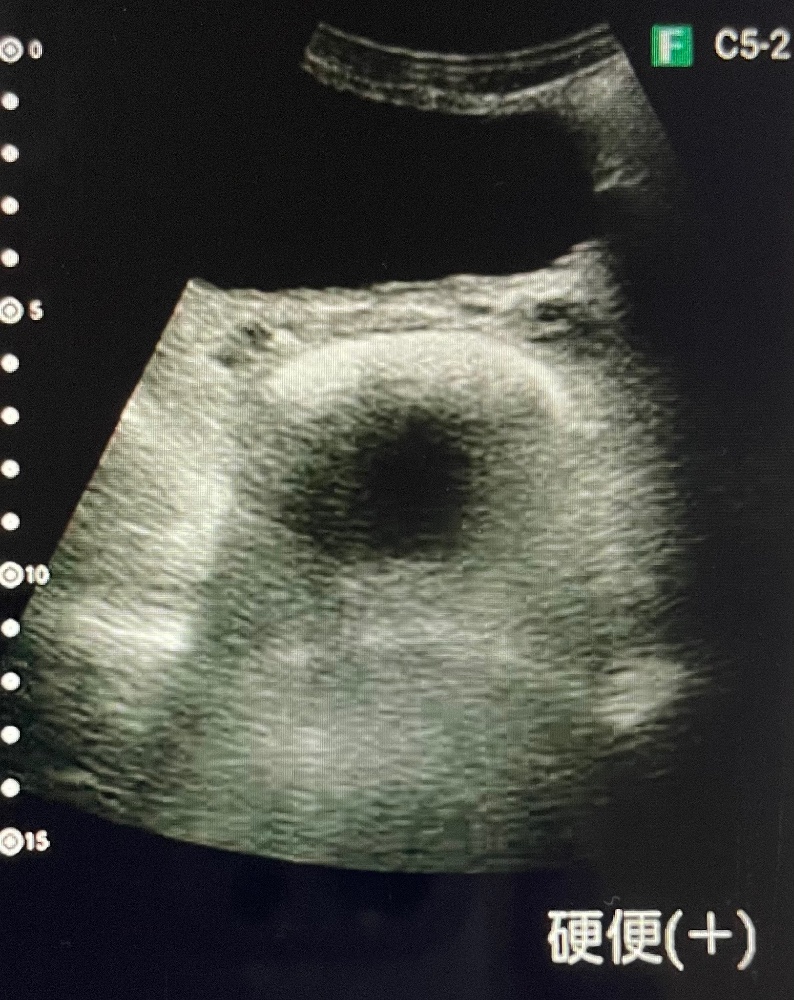

エコーを活用した看護を実践しています

↓画像をタップすると拡大します🔍